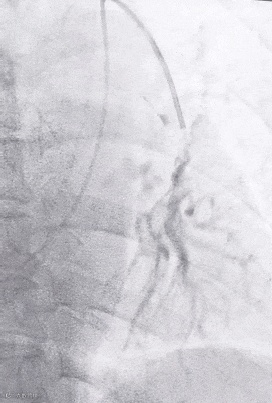

SWAM技术在肺动脉栓塞PE中的应用:

天航抽吸导管有着极强抗弯折能力及优异的支撑性,结合7mm天戟分离器可精准定位靶病变,血栓清除效果显著。